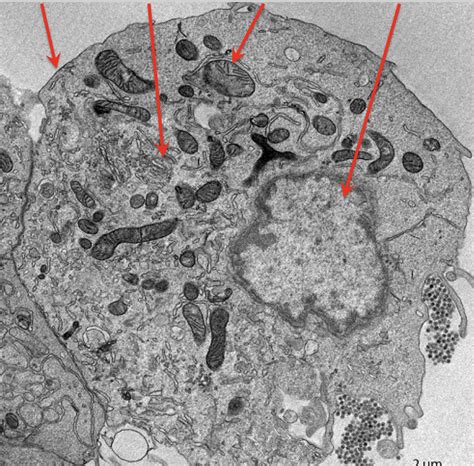

Alright, let’s kick things off with the absolute basics, shall we? Pseuoschistosome side 13 is, at its core, a type of parasitic worm. When we talk about parasites, we’re generally referring to organisms that live on or inside another organism, called a host, and benefit by deriving nutrients at the host’s expense. Pseuoschistosomes are part of a larger group of flatworms, and the specific ‘side 13’ designation often refers to a particular strain, species, or even a specific genetic marker that scientists use to differentiate it from others in its family. Think of it like having different breeds of dogs – they’re all dogs, but they have distinct characteristics. Similarly, Pseuoschistosome side 13 has its own unique features that set it apart. Its life cycle is typically complex, involving multiple hosts and different developmental stages. This complexity is a hallmark of many parasites and is a key area of study for researchers trying to understand how they survive and spread. The ‘side 13’ might come from how it was first identified or a specific genetic sequencing result, helping scientists pinpoint its identity. This level of detail is crucial for tracking its presence, understanding its behavior, and developing strategies to manage any associated health concerns. It’s not just a random label; it’s a scientific identifier that unlocks a wealth of information about the parasite’s lineage and characteristics. So, when you hear ‘Pseuoschistosome side 13,’ picture a very specific, uniquely identified parasitic flatworm with a potentially intricate life story. This specificity is what allows for targeted research and intervention, making it a vital point of focus in parasitology. We’re talking about a microscopic marvel of adaptation, and ‘side 13’ is just the key to unlocking its specific biological narrative. It’s the difference between knowing you have a cold and knowing you have a specific strain of the rhinovirus – precision matters in science!

Now, let’s get into the really fascinating stuff: the life cycle of Pseuoschistosome side 13 . Parasites are masters of survival, and their life cycles are often incredibly complex, designed to ensure they can reproduce and spread effectively. For Pseuoschistosome side 13, this typically involves at least two different host species. Usually, there’s an intermediate host, which is often a snail or another mollusk, and a definitive host, which is where the parasite reaches sexual maturity and reproduces, often a vertebrate like a fish, bird, or even a mammal. The cycle might start with eggs being shed into the environment, perhaps in water or feces. These eggs hatch into a larval stage, which then needs to infect the intermediate host – let’s say, a specific type of snail. Inside the snail, the parasite undergoes significant development and multiplication, often through several more larval stages. This is where the ‘side 13’ might be particularly relevant, as certain genetic variations could influence its infectivity or development within specific snail species. Once it’s developed sufficiently within the snail, a new larval form emerges, ready to infect the definitive host. This stage is often the one that poses a potential risk. For instance, if humans accidentally ingest contaminated water or come into contact with infected intermediate hosts, they could become infected. Inside the definitive host, the parasite matures into an adult worm, mates, and lays eggs, thus completing the cycle and perpetuating the species. Understanding each step – from egg to larva to infective stage – is crucial for figuring out how to break the cycle. This might involve controlling the snail population, improving sanitation to prevent contamination, or educating communities about the risks. The ‘side 13’ designation can be vital here, as different strains might prefer different hosts or have varying levels of infectivity, requiring tailored control strategies. It’s a delicate dance of adaptation and survival, and studying this cycle gives us the upper hand in preventing infections. The sheer ingenuity of these organisms in navigating their multi-host existence is truly remarkable, showcasing nature’s relentless drive for continuation. Each stage is a critical bottleneck, and Pseuoschistosome side 13 has evolved to overcome them all.